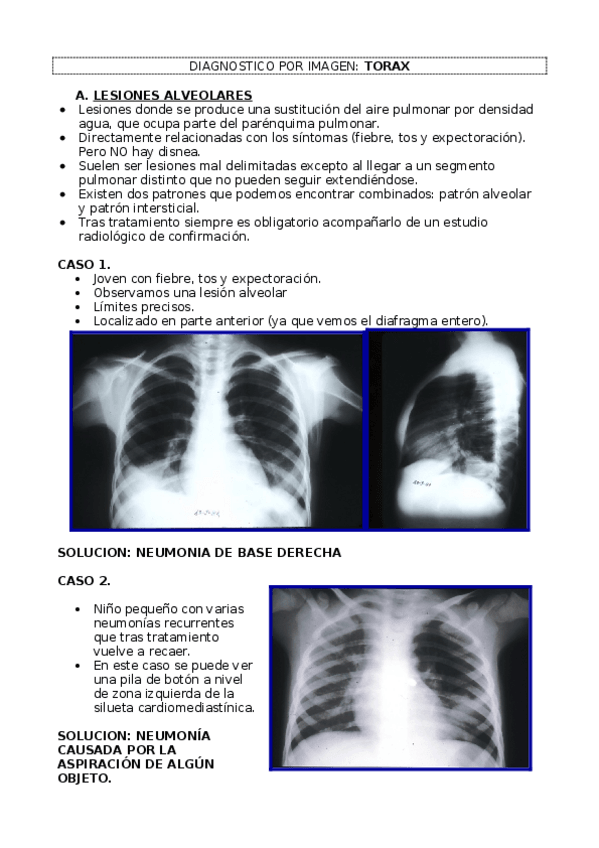

He publicado nuevos apuntes de 4º Diagnóstico Por Imagen: DX IMAGEN. TORAX.docx